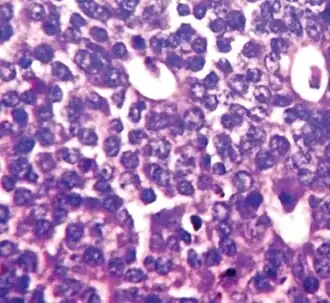

Nuclear pleomorphism

This parameter assesses whether the cell nuclei are uniform like those in normal breast duct epithelial cells, or whether they are larger, darker, or irregular (pleomorphic). In cancer, the mechanisms that control genes and chromosomes in the nucleus break down, and irregular nuclei and pleomorphic changes are signs of abnormal cell reproduction.

Note: The cancer areas having cells with the greatest cellular abnormalities should be evaluated.

- 1 point: nuclei with minimal or mild variation in size and shape

- 2 points: nuclei with moderate variation in size and shape

- 3 points: nuclei with marked variation in size and shape

Invasive ductal carcinoma with marked nuclear pleomorphism.